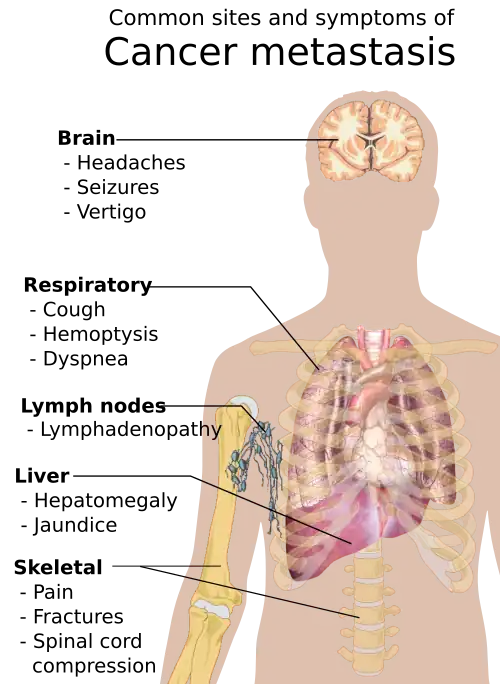

Metastasis is the spread of cancer to other locations in the body. The dispersed tumors are called metastatic tumors, while the original is called the primary tumor. Almost all cancers can metastasize.[40] Most cancer deaths are due to cancer that has metastasized.[41]

Metastasis is common in the late stages of cancer and it can occur via the blood or the lymphatic system or both. The typical steps in metastasis are:

Different types of cancers tend to metastasize to particular organs. Overall, the most common places for metastases to occur are the lungs, liver, brain, and the bones.[40]

Metastasis

Metastasis is common in the late stages of cancer and it can occur via the blood or the lymphatic system or both. The typical steps in metastasis are local invasion, intravasation into the blood or lymph, circulation through the body, extravasation into the new tissue, proliferation and angiogenesis. Different types of cancers tend to metastasize to particular organs, but overall the most common places for metastases to occur are the lungs, liver, brain and the bones.[40]